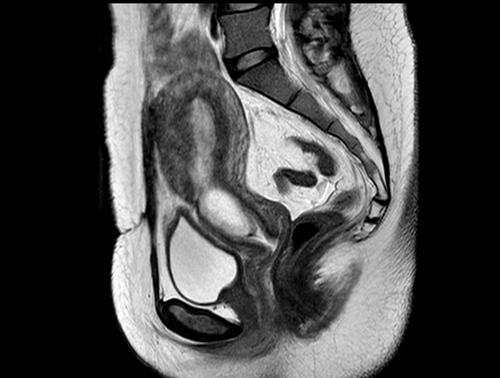

2024-11-06盆腔磁共振平扫+增强+功能成像:子宫下段至宫颈处妊娠囊,部分突入子宫剖宫产瘢痕处,考虑瘢痕妊娠(Ⅱ型)(见图1)。

图1 患者盆腔MRI